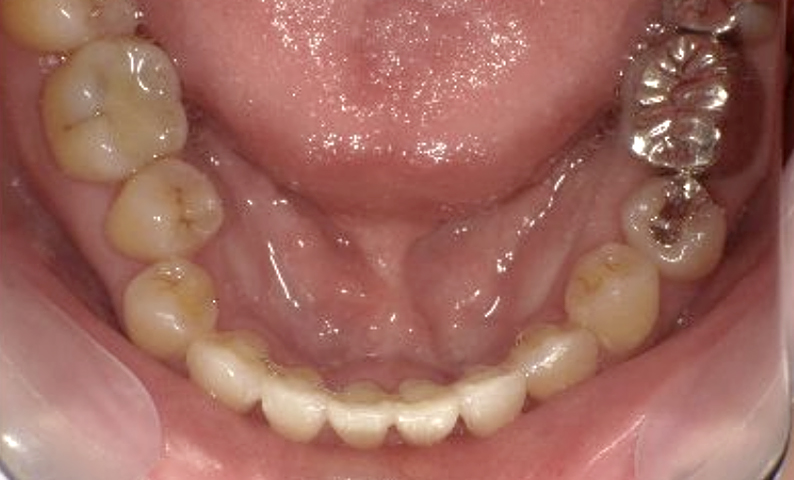

症例_003 下顎だけの部分矯正

治療期間:10ヶ月金額:24万円+税女性前歯のガタガタ下の前歯だけ上顎は補綴治療中

| Before | After |